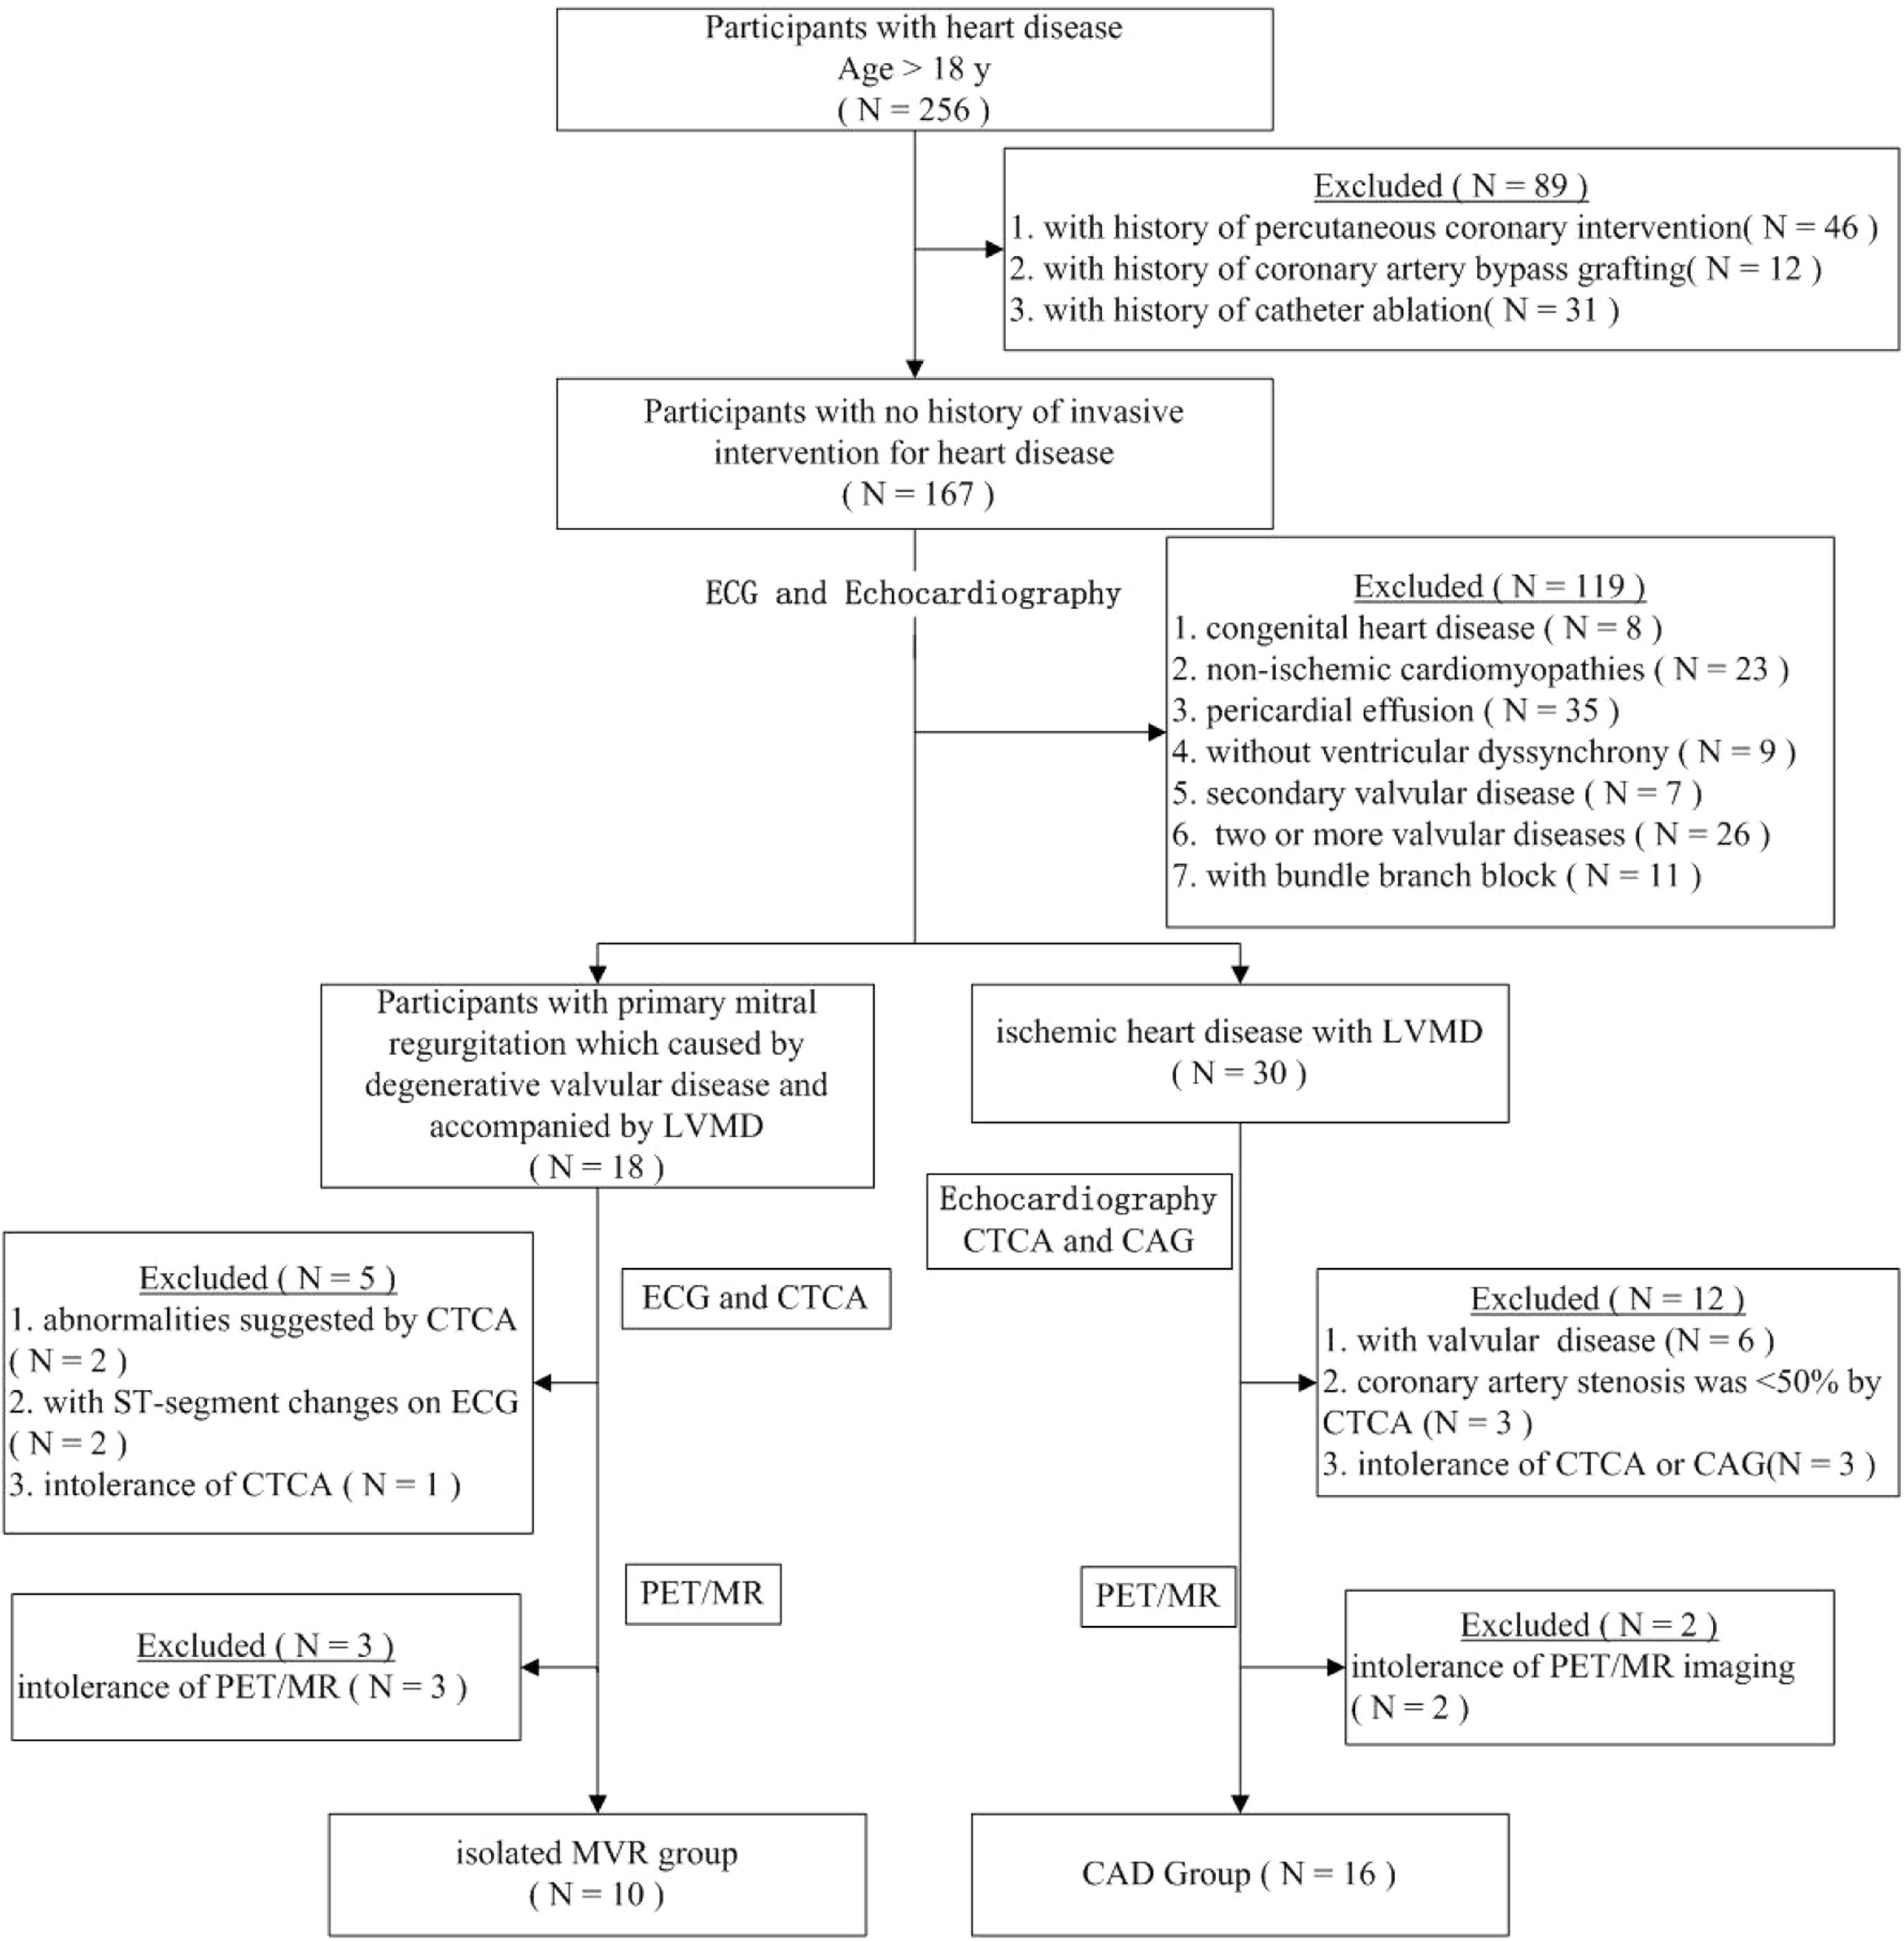

Additionally, age- and sex-matched individuals with no echocardiographic evidence of cardiovascular or other metabolic diseases and those who had not undergone invasive cardiac intervention were included as controls. All enrolled participants underwent cardiac 18F-AlF-FAPI PET/MR imaging (Fig. 1). This study was approved by the Ethics Committee of the General Hospital of Northern Theater Command (Y2021–012) and was conducted in accordance with the guidelines outlined in the Declaration of Helsinki. Written informed consent was obtained from all the participants.

ResultsStudy cohortAmong the 256 patients with heart diseases, 89 who had undergone invasive interventions were excluded (percutaneous coronary intervention [n = 46], coronary artery bypass grafting [n = 12], and radiofrequency ablation [n = 31]). The remaining 167 patients, without a history of invasive intervention for heart disease, were screened using echocardiography. Based on the echocardiogram results, 52 patients with the following conditions were excluded (congenital heart disease [n = 8], cardiomyopathy [n = 23], pericardial effusion [n = 35], and combination of valvular and ischemic heart disease [n = 41]). The remaining participants were divided into two groups: patients with valvular disease and LVMD (n = 39) and patients with ischemic heart disease and LVMD (n = 21). Furthermore, after excluding 26 patients with two or more valvular diseases in the valvular disease group, the remaining 13 patients were included in the isolated DMVR group. Of the 21 patients in the ischemic heart disease group, 18 were included in the pure CAD group after exclusion of three patients who were intolerant to CTA examination. Moreover, three and two patients from the isolated DMVR and pure CAD groups, respectively, were excluded owing to intolerance to CMR examination. Finally, 10 patients with DMVR were included in the group of isolated DMVR (mean age, 57 ± 15 years). The CAD group included 16 patients (mean age, 62 ± 10 years). Additionally, 11 age- and sex-matched healthy volunteers (mean age, 54 ± 7 years) were included as controls. The detailed characteristics of the participants are summarized in Table 1 and Fig. 1.